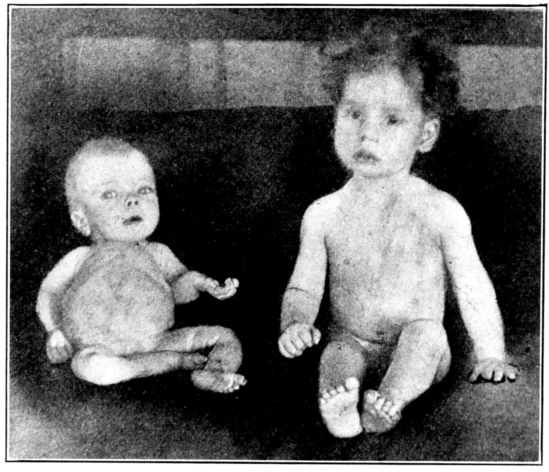

| 141. | Rachitic and normal babies of the same age | 381 |

| 142. | Chest walls of normal and rachitic rats of the same age | 383 |